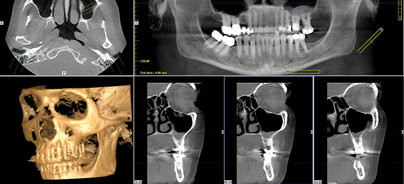

Im Bereich der Implantologie kam die DGZMK zum Schluss, dass eine com­putergestützte Planung auf der Basis dreidimensionaler Röntgenverfahren mithilfe der DVT durchgeführt werden sollte. Jedoch da, bedingt durch die hohe Absorption eines Titanimplantates im weiteren Strahlengang Auf­härtungsartefakte entstehen, ist die Evaluation der unmittelbaren periimplantären Region sowie der Region zwischen Impantaten in Strahlengangsrichtung nur sehr eingeschränkt möglich (Abb. 4).